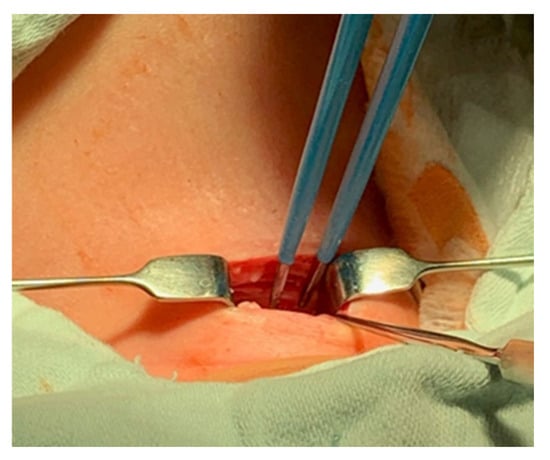

- The platysma is reached, and its muscles are separated and retracted using retractors (Figure 3).